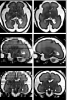

Fbrain is a ERC funded project. The purpose of this project is to develop image processing tools for a better understanding of the fetal brain development.

BTK (baby brain toolkit), which is the toolkit developed for the fbrain project, consists of several image processing tools: image reconstruction, image denoising, image segmentation, tractography etc.